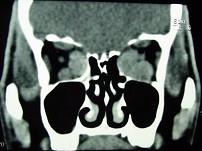

问题 男,52岁,双眼突出2-3年,请结合影像图像,选择最可能的诊断 ( )

选项 A、眼型Graves病 B、动静脉瘘合并眼外肌增粗 C、肌炎型炎性假瘤 D、眼肌发育异常 E、淋巴瘤

答案 A